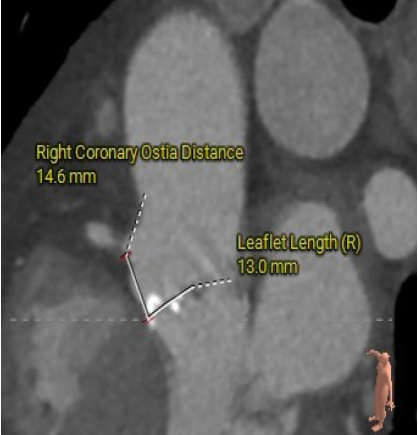

右冠开口高度13.1mm

冠脉开口及瓣叶长度评估